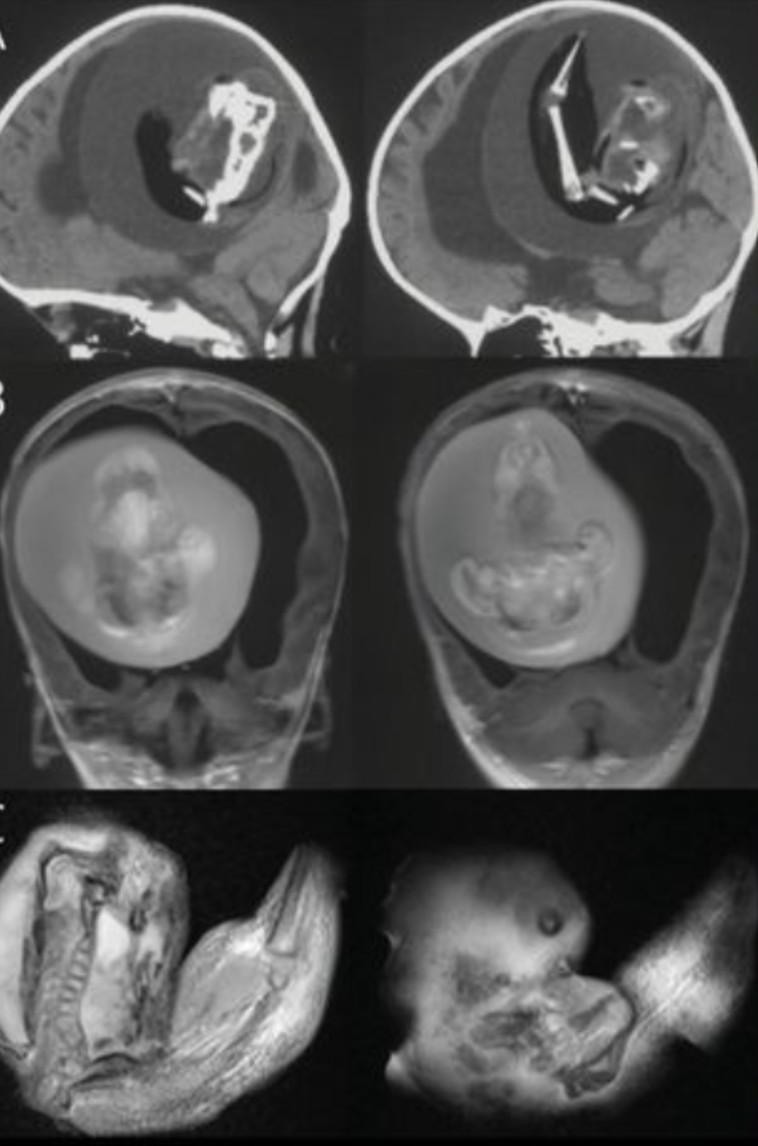

תוכן מטריד וקשה לקריאה: רופאים בבית החולים Huashan באוניברסיטת פודן בסין, גילו כי תינוקת שנולדה עם ראש גדול בצורה יוצרת דופן, נשאה למעשה את האח התאום הזהה שלה בגולגולת. התאום שאותר, המשיך לגדול בראשה של אחותו במשך חודשים, וכבר היה בשלב מתקדם של התפתחות עם גפיים עליונות, עצמות וציפורניים. התופעה מוכרת בתור "עובר בתוך עובר" והיא נדירה להפליא, כך שרק 200 מקרים דומים נרשמו אי פעם.

רק כשנה לאחר לידתה של התינוקת, התגלה אחיה התאום. הוריה של הפעוטה היו מודאגים לגבי ראשה והכישורים המוטוריים המשונים שלה, ולכן פנו לבית החולים הושאן באוניברסיטת פודן בסין. הילדה, שזהותה לא נחשפה, עברה סריקת CT שחשפה תמונות מזעזעות של התאום שטרם נולד, כשהוא מפיל לחץ על מוחה.

באופן מחריד למדי, כשאותר, התאום עדיין היה בחיים. לדברי הרופאים, הוא הצליח לשרוד כל הזמן הזה כשחלק את אספקת הדם עם אחותו. עם זאת, היה צורך דחוף להסירו בניתוח מאחר והפעוטה פיתחה "הידרוצפלוס" - הגורמת להצטברות נוזלים במוח, ראש מוגדל, עייפות קיצונית והתקפי כאב קשים.